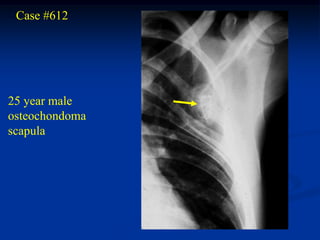

Case #612

25 year male

osteochondoma

scapula

Scapular view